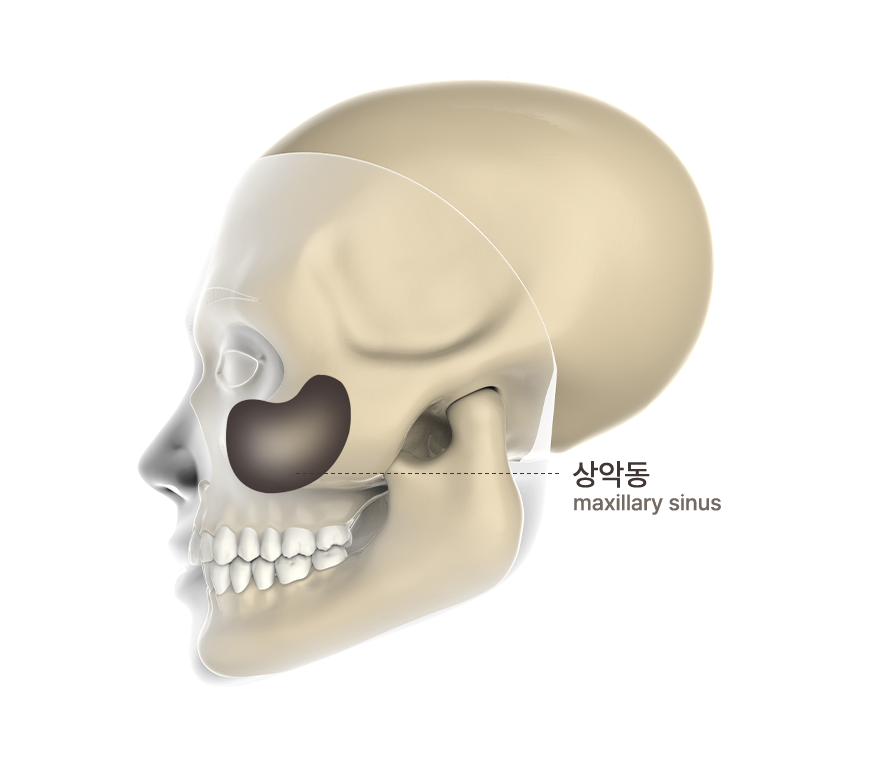

상악동이란?

사람의 얼굴 뼈, 양 볼 안쪽에 있는 빈 공간으로 소리의 공명을 일으키며 공기의 노폐물과 먼지를 걸러내고 두개골의 무게를 줄여주는 역할을 합니다.  위턱 어금니 부위에 임플란트 시 치조골량이 부족한 것이 대부분인데 이는 상악동의 빈 공간 때문입니다. 상악동은 얇은 미세한 막으로 둘러싸여 있는데 이 막을 들어 올린 후 그 부위에 치조골을 이식하여 임플란트를 심을 바탕을 마련해 주는데, 이러한 수술을 상악동 수술을 동반한 임플란트라고 표현합니다.